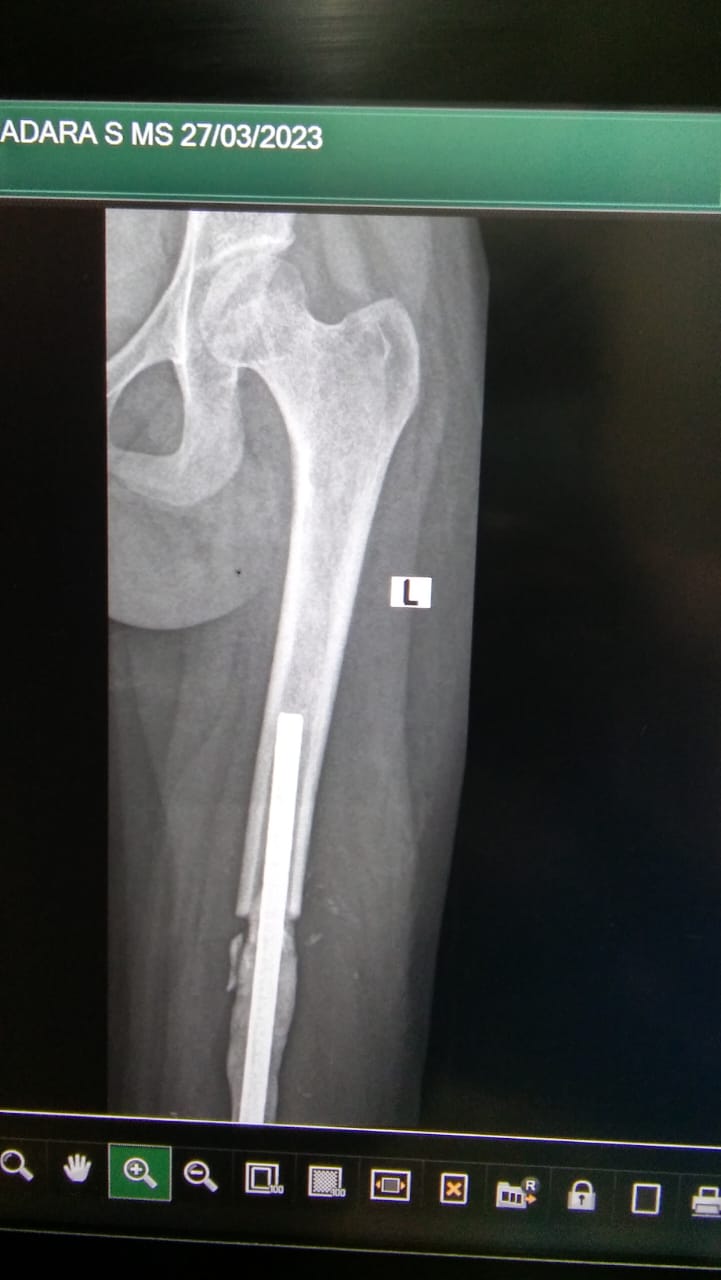

G V S Madara, 19 years old girl, was diagnosed with osteosarcoma (born cancer) of the left distal femur. The surgery of megaprosthesis fixation (artificial joint replacement) was done after the completion of her chemotherapies. The trust contributed towards expenses for his treatment.